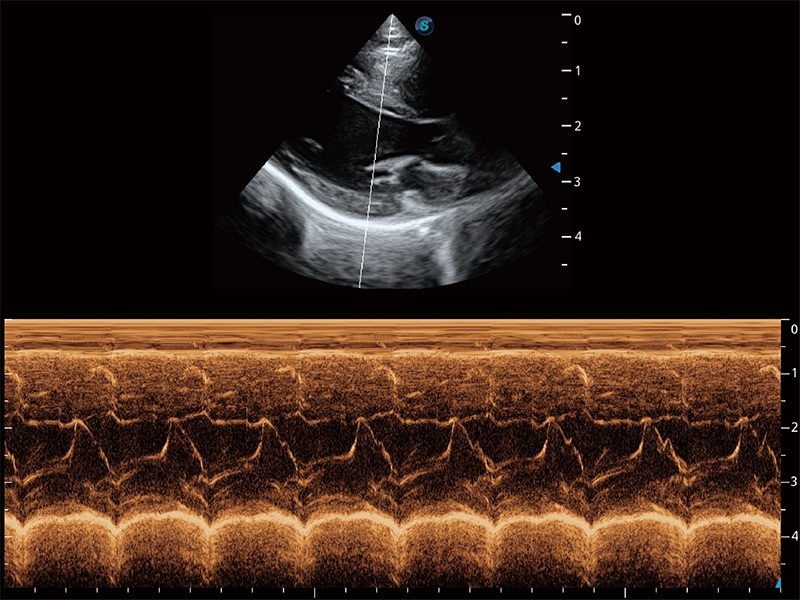

通過360度任意調(diào)節(jié)3條M型取樣線,在同一心動(dòng)周期上觀察心臟不同位置的運(yùn)動(dòng)曲線,得到準(zhǔn)確的心功能測(cè)量數(shù)據(jù),有效評(píng)估心肌運(yùn)動(dòng)及左心室功能。